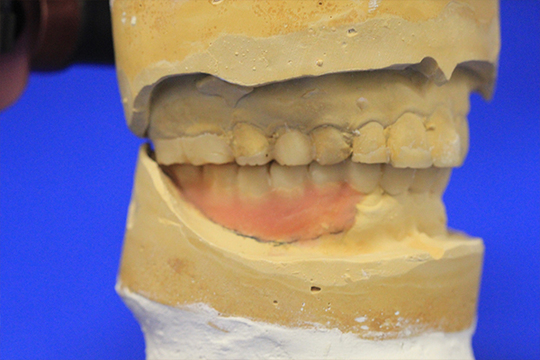

ディグマのデータを元に模型上で理想的な口腔内を再現します。